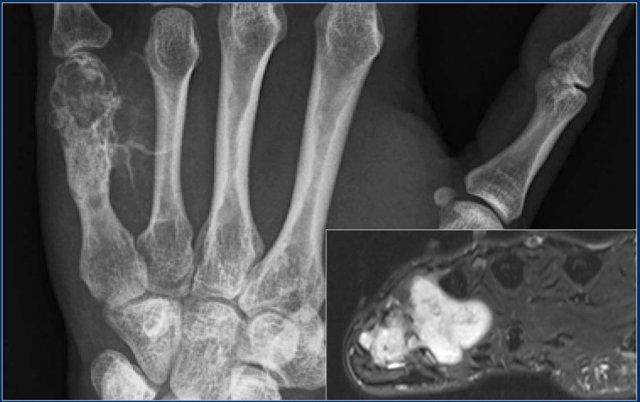

Đây là bệnh nhân nam 44 tuổi với khối u hỗn hợp tiêu xương và đặc xương xuất phát từ xương đốt bàn tay thứ năm.

Có các dải vôi hóa trong phần mềm.

Hình ảnh MRI axial trọng số T2 cho thấy tín hiệu cao của khối u trong xương đốt bàn tay với sự lan rộng của khối mô mềm có thùy.

Diagnosis: chondrosarcoma grade 2